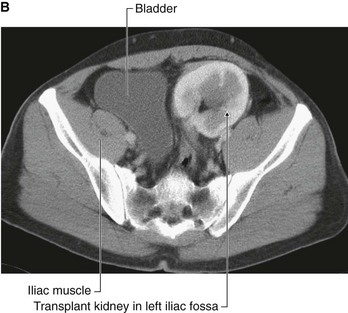

Kidney transplant

Kidney transplantation began in the United States in the 1950s. Since the first transplant, the major problem for kidney transplantation has been tissue rejection. A number of years have passed since this initial procedure and there have been significant breakthroughs in transplant rejection medicine. Renal transplantation is now a common procedure undertaken in patients with end stage renal failure.

Transplant kidneys are obtained from either living or deceased donors. The living donors are carefully assessed, because harvesting a kidney from a normal healthy individual, even with modern day medicine, carries a small risk.

Deceased kidney donors are brain dead or have suffered cardiac death. The donor kidney is harvested with a small cuff of aortic and venous tissue. The ureter is also harvested.

An ideal place to situate the transplant kidney is in the left or the right iliac fossa (Fig. 4.146). A curvilinear incision is made paralleling the iliac crest and pubic symphysis. The external oblique muscle, internal oblique muscle, transverse abdominis muscle, and transversalis fascia are divided. The surgeon identifies the parietal peritoneum but does not enter the peritoneal cavity. The parietal peritoneum is medially retracted to reveal the external iliac artery, external iliac vein, and the bladder. In some instances the internal iliac artery of the recipient is mobilized and anastomosed directly as an end-to-end procedure onto the renal artery of the donor kidney. Similarly the internal iliac vein is anastomosed to the donor vein. In the presence of a small aortic cuff of tissue the donor artery is anastomosed to the recipient external iliac artery and similarly for the venous anastomosis. The ureter is easily tunneled obliquely through the bladder wall with a straightforward anastomosis.

image image

Fig. 4.146 Kidney transplant. A. This image demonstrates an MR angiogram of the bifurcation of the aorta. Attaching to the left external iliac artery is the donor artery for a kidney that has been transplanted into the left iliac fossa. B. Abdominal computed tomogram, in the axial plane, showing the transplanted kidney in the left iliac fossa.

The left and right iliac fossae are ideal locations for the transplant kidney, because a new space can be created without compromise to other structures. The great advantage of this procedure is the proximity to the anterior abdominal wall, which permits easy ultrasound visualization of the kidney and permits Doppler vascular assessment. Furthermore, in this position biopsies are easily obtained. The extraperitoneal approach enables patients to make a swift recovery.